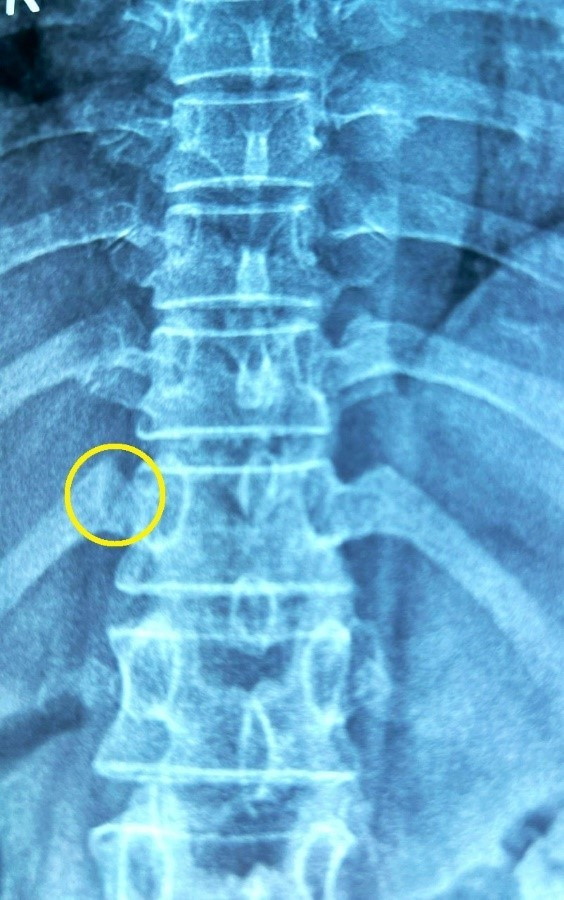

Tại bệnh viện, kết quả chụp phim cho thấy bà A. bị gãy xương sườn 12 phạm khớp sườn cột sống. Do không có mảng sườn di động không ảnh hưởng chức năng hô hấp. Các bác sĩ cho toa thuốc, nghỉ ngơi 1 tháng, hạn chế cử động vùng thân để xương sườn chóng lành. Khi tình trạng ổn, tiếp tục tiến hành chữa đau thắt lưng và thoát vị đĩa đệm.

Bà A. bị tổn thương sau khi thực hiện bấm huyện và bẻ khớp. Ảnh: BVCC